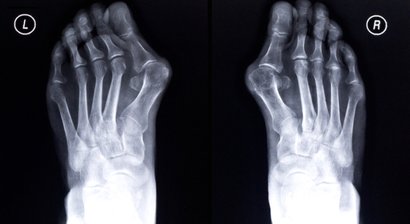

Als Facharzt für Orthopädie und Orthopädische Chirurgie habe ich mich insbesondere auf die Prävention, Abklärung und Behandlung von Verletzungen, Erkrankungen und Fehlstellungen des Fußes spezialisiert, darunter Fußschmerzen, Metatarsalgie, Hallux valgus und rigidus, Hammer- und Krallenzehen, Arthrosen, Erkrankungen und Rupturen der Achillessehne, Bänderinstabilität, Probleme mit dem Sprunggelenk, Senk-, Platt- und Spreizfuß und viele andere. Ein weiterer Behandlungsschwerpunkt ist die Kniegelenksarthroskopie.

Hallux valgus